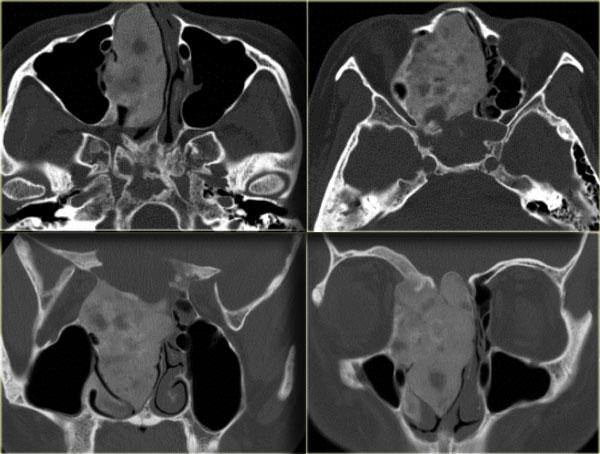

Hình ảnh bên trái của một bệnh nhân khác được đọc là có u mô mềm (mũi tên vàng) ở phía trước xương thái dương.

Đây là các hình ảnh CT cắt ngang tương ứng cho thấy hình ảnh loạn sản xơ điển hình của cánh xương bướm.

Chẩn đoán phân biệt cần đặt ra là u màng não (meningioma).